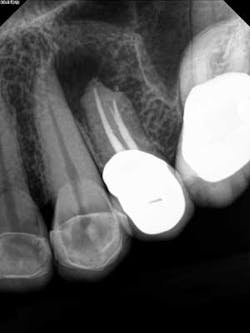

Fig. 3The patient did not want to lose her tooth and was referred back to the specialist for an evaluation and consideration of options. It was discussed and recommended that the patient have root end resection with a root end filling (apicoectomy). She agreed, and the treatment was completed. There was suspicion as to the nature of the pathology of the cyst-like lesion, so it was sent out for biopsy. Diagnosis was chronic, localized osteitis and actinomyces colony. Conclusively, the source of the infection was eradicated but the presence of the actinomyces microorganism was enough to sustain a chronic infection post-initial RCT. (Fig. 4)

Fig. 4A two-month follow-up with the patient revealed a recovery of the area with loss of pressure and pain. A radiograph of the area showed initial stages of healing and bone recovery. She has been placed on a recall program for continuous assessment of the area. Prognosis is good. (Fig. 5)